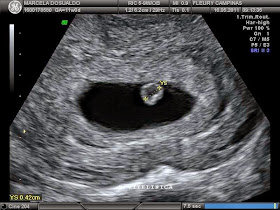

Ultrassonografia transvaginal – Procedimento de menor custo, que

permite a identificação de endometriomas, aderências pélvicas e

endometriose profunda.